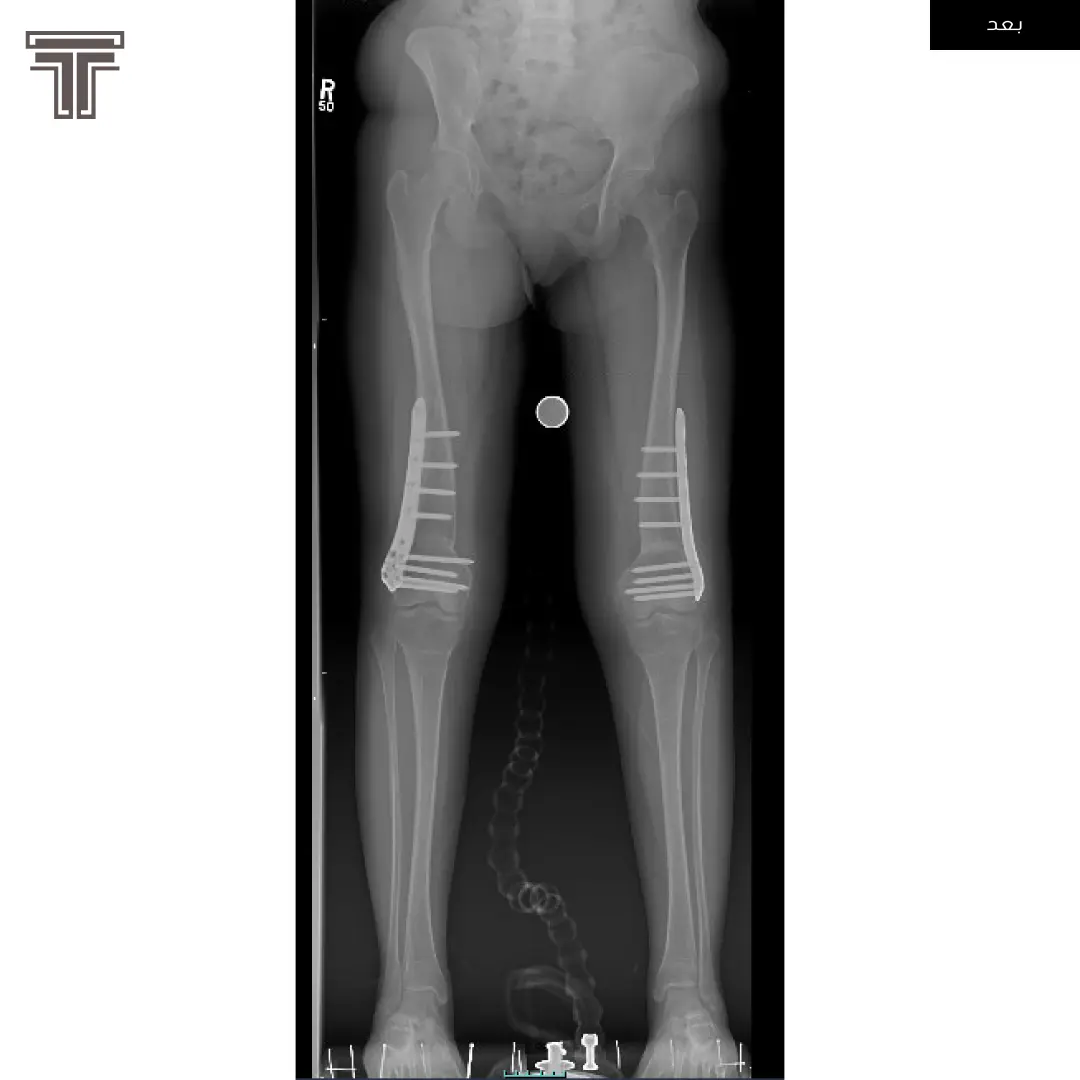

عندما تهمل خلوع الورك الولادية لعمر كبير يصبح علاجها وارجاعها صعب ويتطلب عملية استبدال للمفصل. وفي مثل هذه العمليات وتحديدا في استبدال مفاصل خلوع الورك الولادية يتطلب تقصير في طول الفخذ لتجنب المضاعفات.